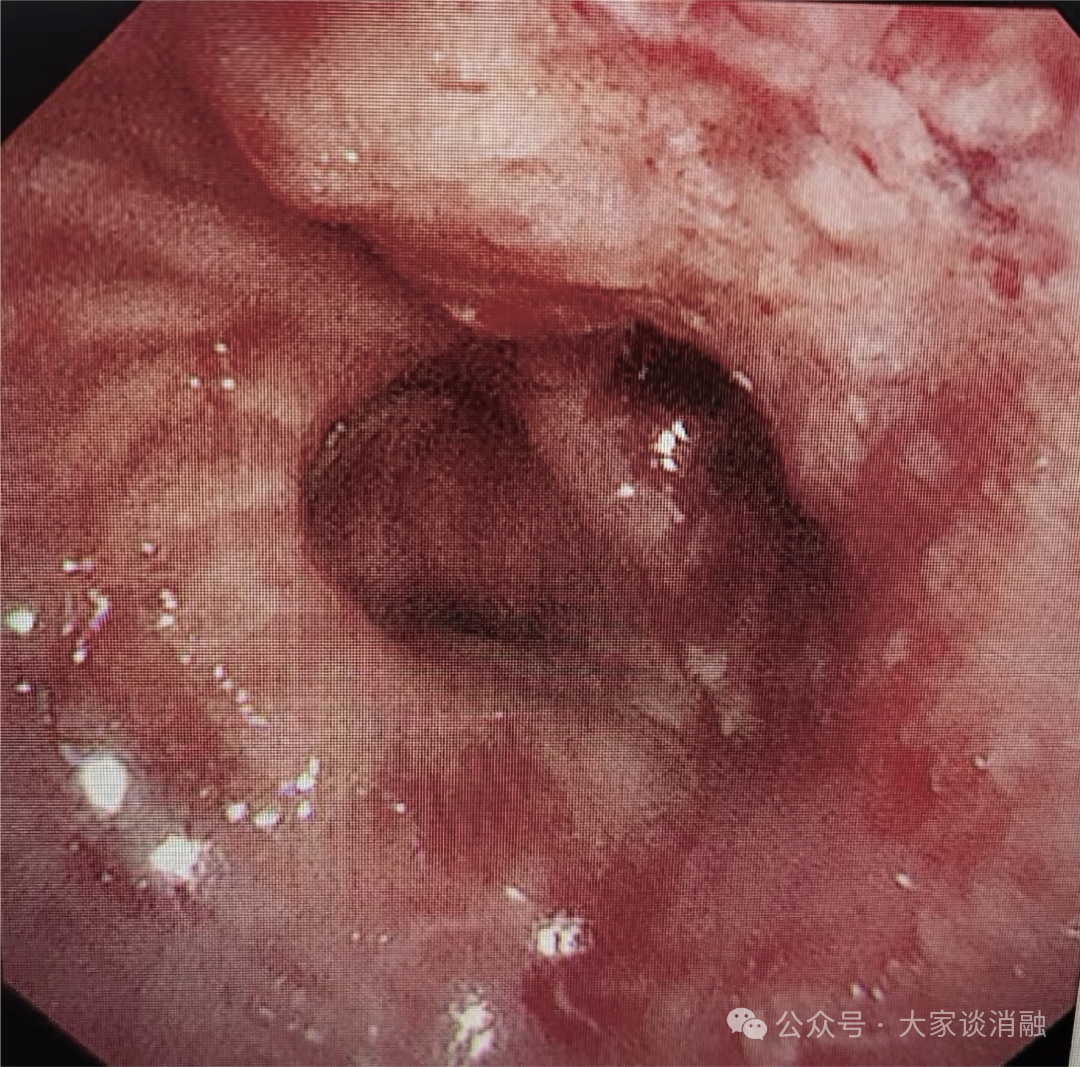

术后

10月24日,邵桂英主任团队为患者进行术后第一次局麻下清坏死组织治疗气道内的肿瘤体积进一步缩小,下叶开口管腔越来越通畅,原本严重的呼吸困难及持续咳嗽症状也明显减轻,患者及家属对治疗效果十分认可